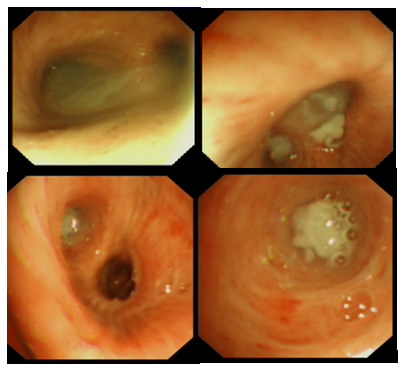

患者感染学指标均基本正常(图1);两下肺存在肺不张,右侧包裹性胸腔积液(图2);呼吸力学指标正常(图3)。纤支镜下可见痰液较多,呈黄色,Ⅱ度黏痰(图4)。

图4 患者纤支镜检查

患者恢复仰卧位后给予气管镜吸痰。